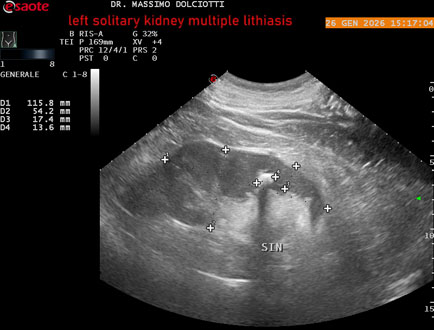

Data inserimento: 29/01/2026

Ecografia del: 26/01/2025

Strumento: Esaote MyLab Eight

Sonda: Conevx Multifrequenza 1-8 MHz

Età Paziente: M 78 anni

Motivazione dell'esame: follow up di litiasi al rene sinistro, in paziente sottoposto a nefrectomia destra.

Commento all'esame: le immagini ed il video documentano il rene sinistro in sede, di ecostruttura disomogenea per evidenza di multiple formazioni litiasiche al pielone superiore, delle dimensioni di 15,9 mm, al pielone medio di 17,5 mm e al pielone inferiore di 18,9 mm e morfovolumetria normale, con diametro bipolare di 115 (v.n. 90-120 mm) x 54 mm e parenchima renale dello spessore di 17 mm ( v.n. > 13 mm).

Conclusioni: litiasi multipla del monorene sinistro (multiple lithiasis of the left solitary kidney).